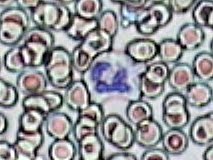

Práctica de Frotis sanguíneo 25